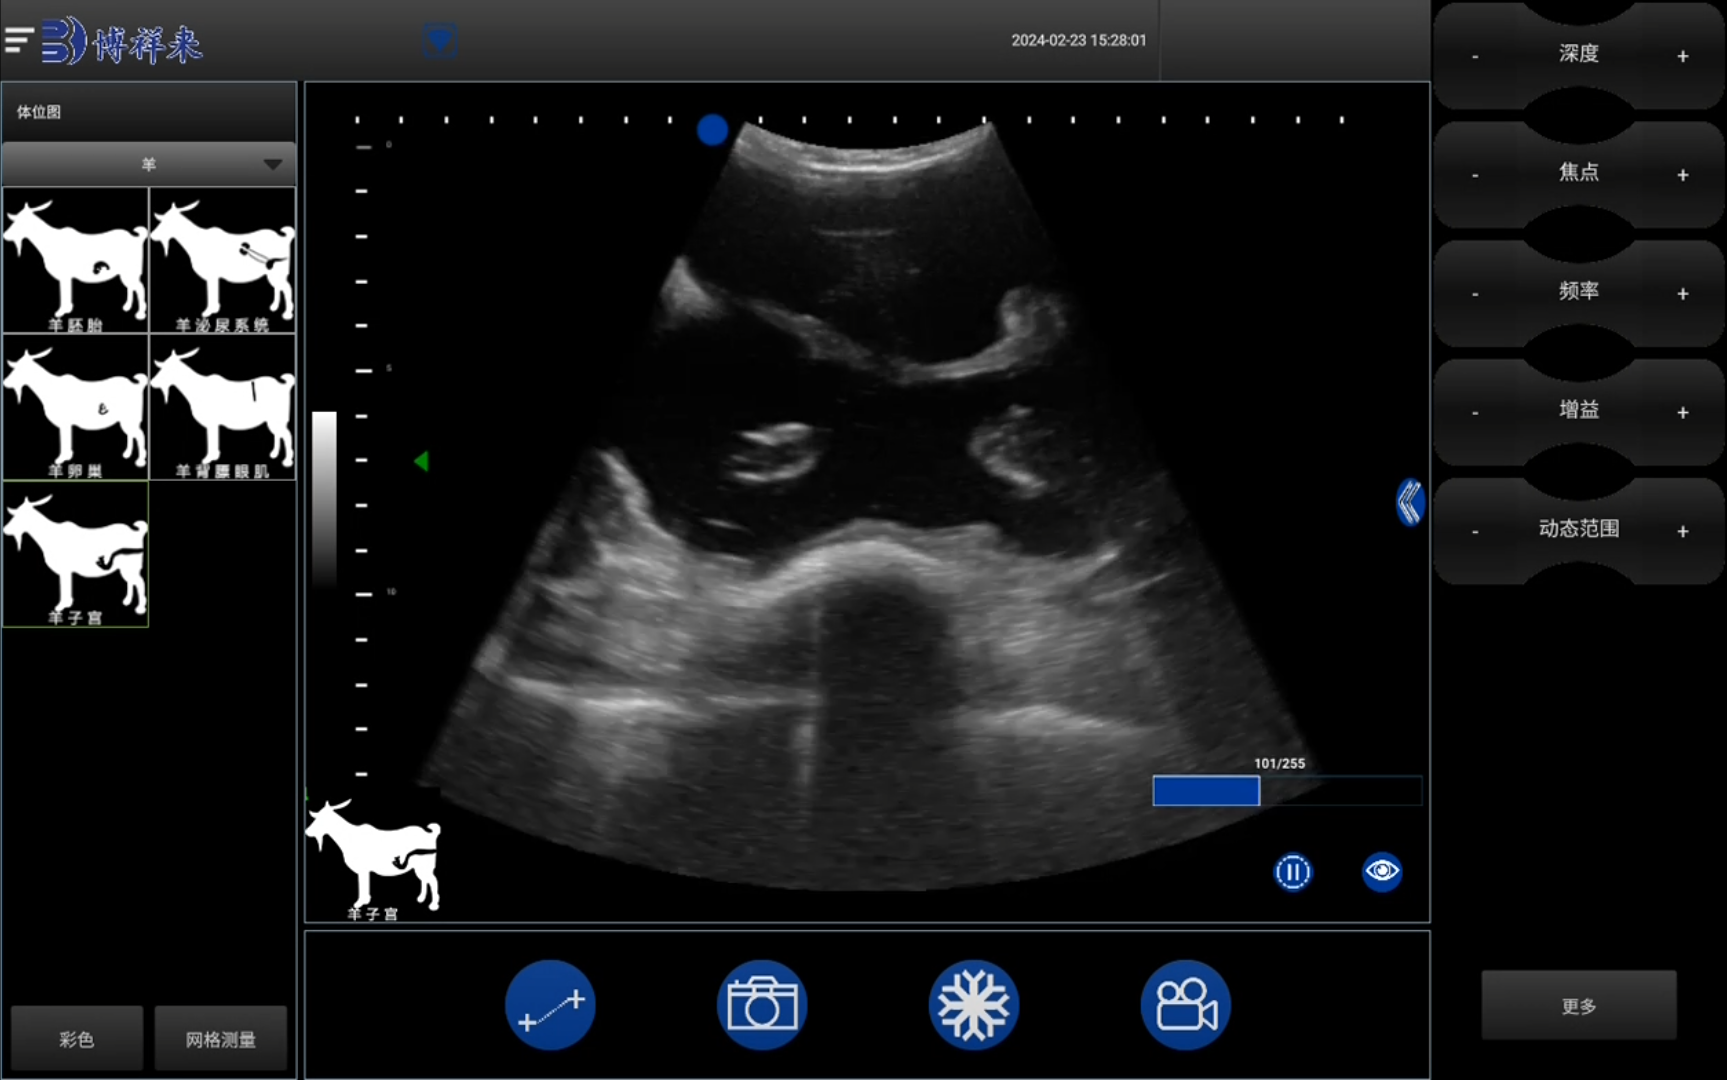

B超机利用超声波原理进行图像扫描,通过探头发射高频声波进入母羊体内,并接收反射回来的信号,从而形成清晰的图像。该图像能够准确显示羊体内的胚胎及其发育情况,特别是胎儿的数量、大小、位置等信息。B超机的优势在于能够在怀孕初期就进行检测,避免了传统方法中可能存在的误差。

在怀孕后期,尤其是45天至60天之间,羊用B超机能够通过详细的图像扫描来确认母羊怀了多少个胎儿。通过对羊腹部的扫描,B超机可以检测到每个胎儿的位置,并通过影像显示出胎儿的大小和形态。一般来说,养殖户可以在这一时期准确得知母羊的怀孕状况,包括胎儿的数量、健康状况等。

除了判断胎儿的数量外,羊用B超机还可以实时监控胎儿的发育情况。例如,超声波图像能够帮助检测胎儿是否存在畸形、是否存在死胎等问题。养殖户可以根据这些信息及时采取相应的措施,提高母羊的繁育成功率。